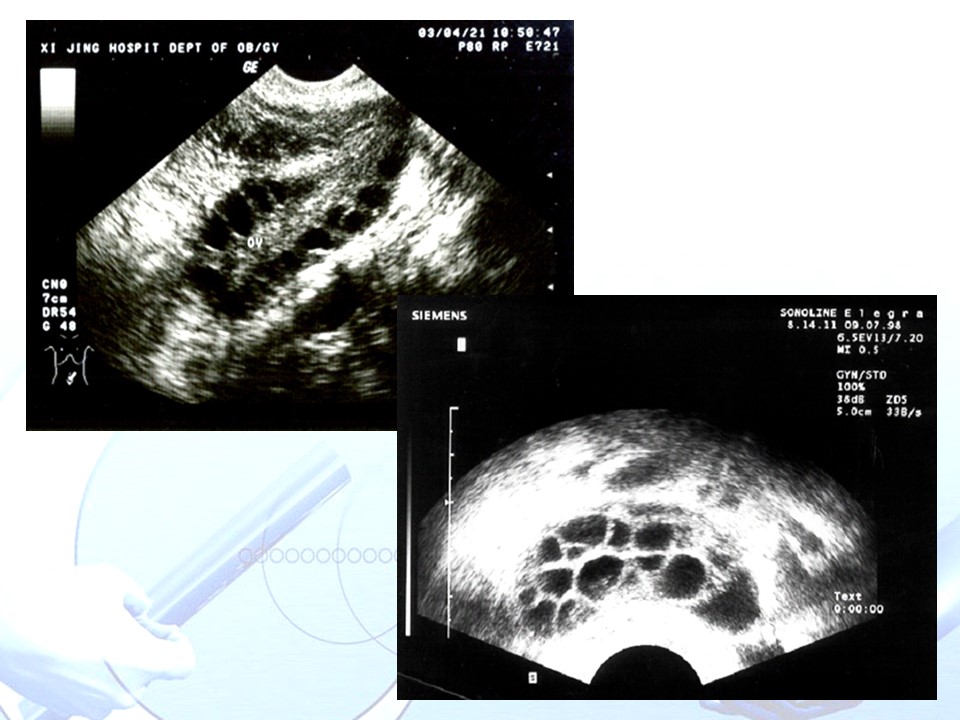

“多囊卵巢综合征PCOS” 的相关文章